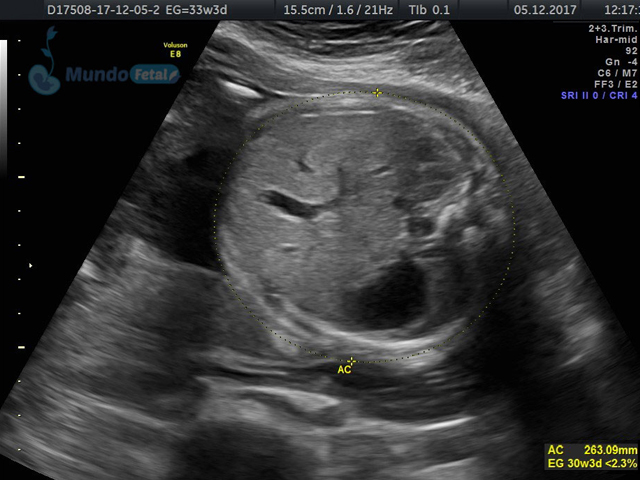

Se recomienda de 32-34 semanas, realizando valoración de crecimiento armónico (4 medidas específicas), valoración anatómica, líquido amniótico, flujos sanguíneos fetales y placentarios perfilando el bienestar fetal hacia el final de embarazo.